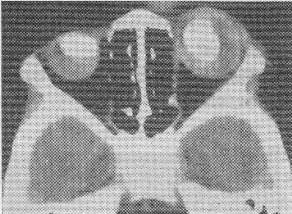

患者男性,53歲,發(fā)現(xiàn)鼻塞及右側(cè)頸部包塊、面部疼痛1個(gè)月余,查體左頸部有一質(zhì)硬的包塊。MRI如圖所示:

正確答案:1.E;2.C 解題思路:鼻咽癌腫瘤在TWI呈與肌肉類似的等信號(hào)或略低信號(hào),TWI呈較高信號(hào),介于肌肉與脂肪組織的信號(hào)之間。本病例結(jié)合臨床表現(xiàn),可診斷為鼻咽癌。鼻咽癌是鼻咽黏膜上皮發(fā)生的癌腫,男性多于女性,已知發(fā)病因素有種族、家族因素,EB病毒感染及環(huán)境致癌因素,由于腫瘤的長(zhǎng)T與放療后纖維化的短T有顯著差異,MR對(duì)鑒別腫瘤復(fù)發(fā)有重要價(jià)值。